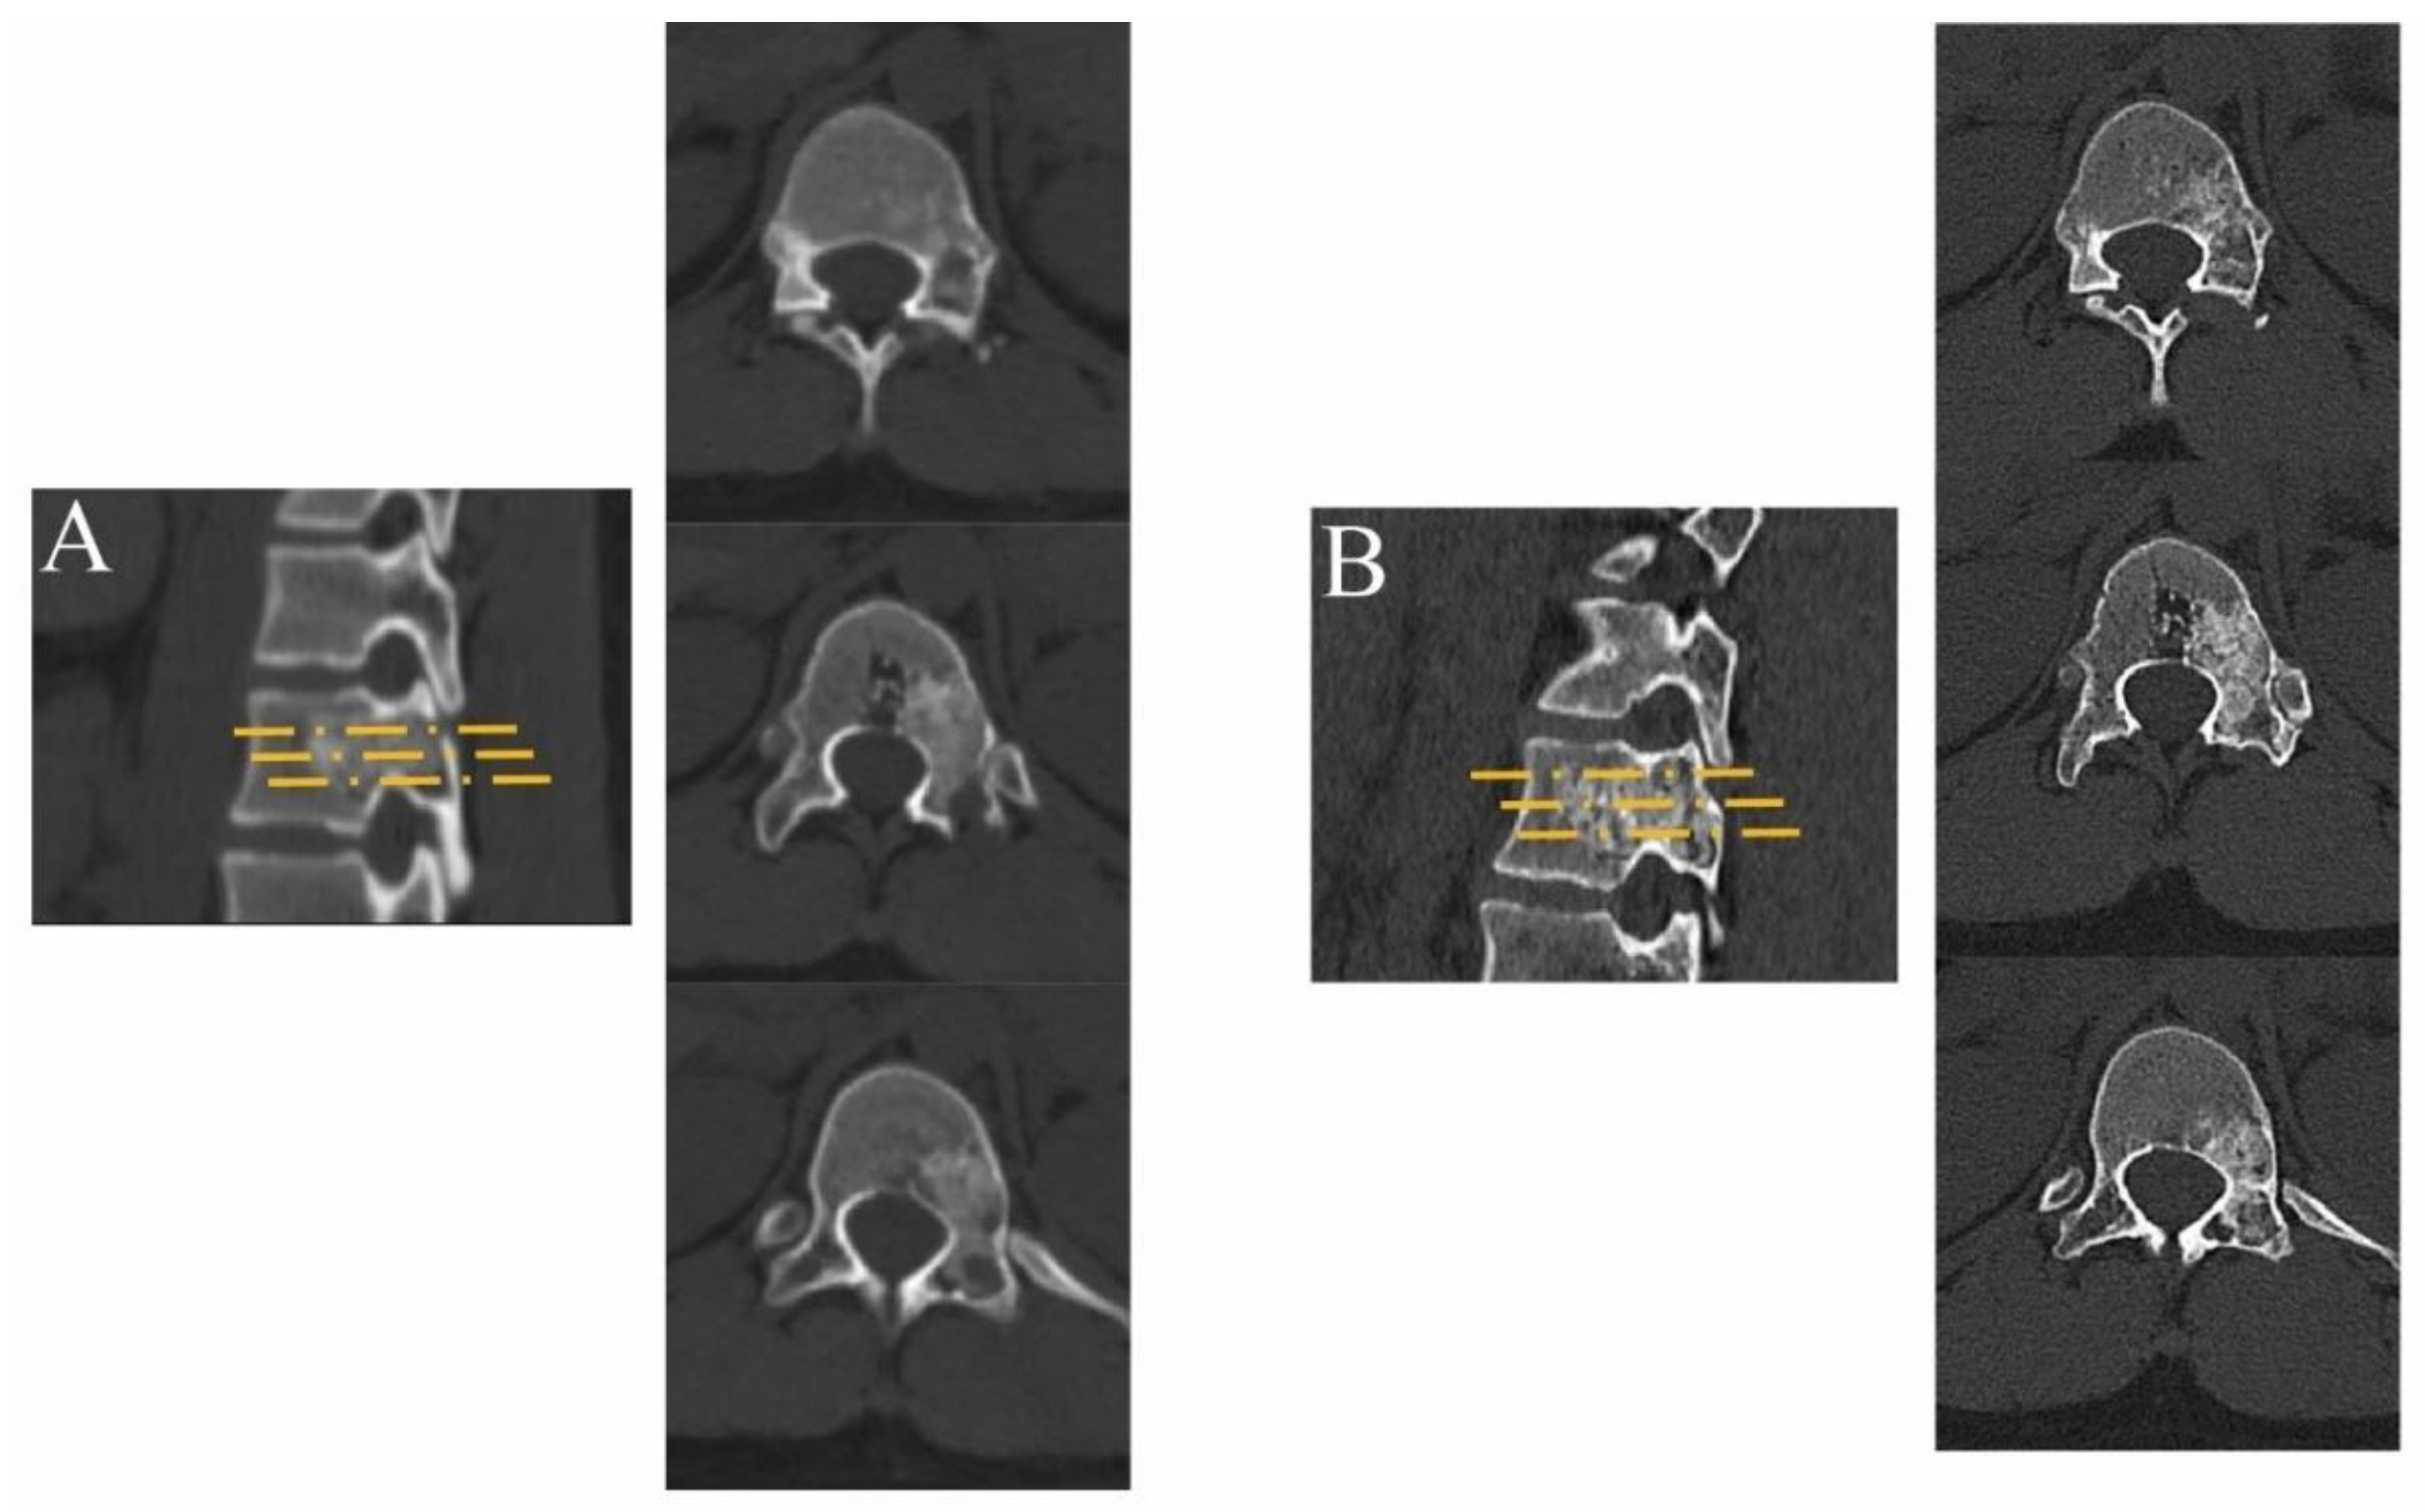

2. Materials and Methods

2.2. Surgical Technique

3. Results